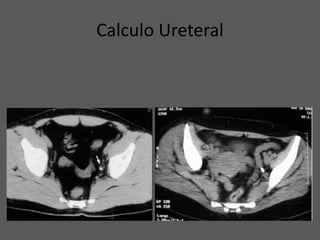

Calculo Ureteral